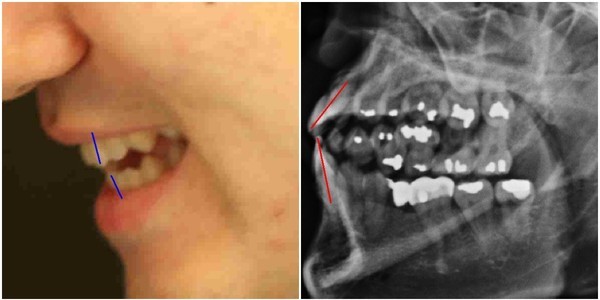

- ▲ 양승오 박사와 치과의사 김우현씨 등, ‘박주신씨 병역비리 의혹’을 제기하고 있는 시민들이, 의혹을 뒷받침하는 근거 중 하나로 지목하고 있는 박주신씨의 치아가 보이는 엑스레이 사진. ⓒ 뉴데일리DB

주신씨의 치아가 보이는 엑스레이에서 드러나는 석연치 않은 의혹, 주신씨의 치아를 치료했다고 주장하는 전 참여연대 운영위 부위원장 출신 치과의사가 검찰에 제출한 증거자료에서 나타나는 ‘유령건강보험증’ 사용 내역, 주신씨 공개신검 당일 현장을 촬영한 서울시 직원의 동영상이 중요 부분에서 편집된 사실 등도, 이 사건 피고인들이 제시하고 있는 주요 증거들이다.

- ▲ ▲ 박주신씨의 치아 상태를 알수 있는 엑스레이 사진 자료. ⓒ 뉴데일리DB

- ▲ ▲ 박주신 엑스레이(X-RAY)에 대한 치의학 박사의 분석자료. ⓒ 뉴데일리DB

양승오 박사 등에 대한 검찰의 수사가 진행되던 지난해, 이 사건 피고인들은 박주신씨 치아 X-Ray를 근거로, 박주신씨의 신체를 촬영했다는 X-Ray 속 피사체가 제3의 인물일 가능성을 주장했다.

주신씨의 치아 X-Ray는 허리 MRI 촬영 과정에서 찍힌 X-Ray 사진들 중에서 치아가 보이는 X-Ray 사진이다.

따라서 치아 X-Ray 상에 나타나는 각종 의혹은, 허리 MRI와 더불어 해당 피사체가 주신씨가 아닐 가능성에 무게를 더한다.

피고인들이 치아 X-Ray를 근거로, '피사체 바꿔치기' 의혹을 강하게 제기한 이유는, X-Ray에 나타난 치아의 상태가, 도저히 20대 중반 청년의 것이라고는 보기 힘든 특징을 갖고 있었기 때문이다.

주신씨 치아 X-Ray 사진을 보면, 치아 상태가 매우 불량하다는 사실을 알 수 있다. 치아 2개는 아예 없고, 아말감으로 때운 치아가 무려 14개에 달한다.

김우현씨는 박주신씨가 자생병원에서 MRI를 촬영하면서 함께 찍은 엑스레이 사진에 의문을 나타냈다.

박주신씨의 치아가 보이는 ‘구외 엑스레이’(이하 치아 엑스레이) 사진에서 나타나는 피사체의 치아상태는 불량하기 짝이 없었다.

도저히 중산층 가정의 20대 청년의 것으로 볼 수 없을 만큼 치아상태가 나빴다.

- ▲ 박주신씨 명의의 치아 엑스레이 사진. ⓒ 뉴데일리DB

김우현씨는 서울 방배동에 살던 20대 청년이 무려 14개에 이르는 치아를 아말감으로 치료 하고, 일부 치아는 아예 빠진 채 몇 년간 방치된 사실에 고개를 가로저었다.

아말감은 수은증기 논란과 변색의 문제점 등으로 1990년대 들어 사용빈도가 급감했다. 2005년경 서울의 중산층 청년이 하나도 아닌 무려 14개의 치아를 아말감으로 치료한다는 것은 상식 밖이었다.

김우현씨는 치과의사로서의 임상경험을 근거로, 자생병원 엑스레이 피사체의 정체에 의문을 가졌다.